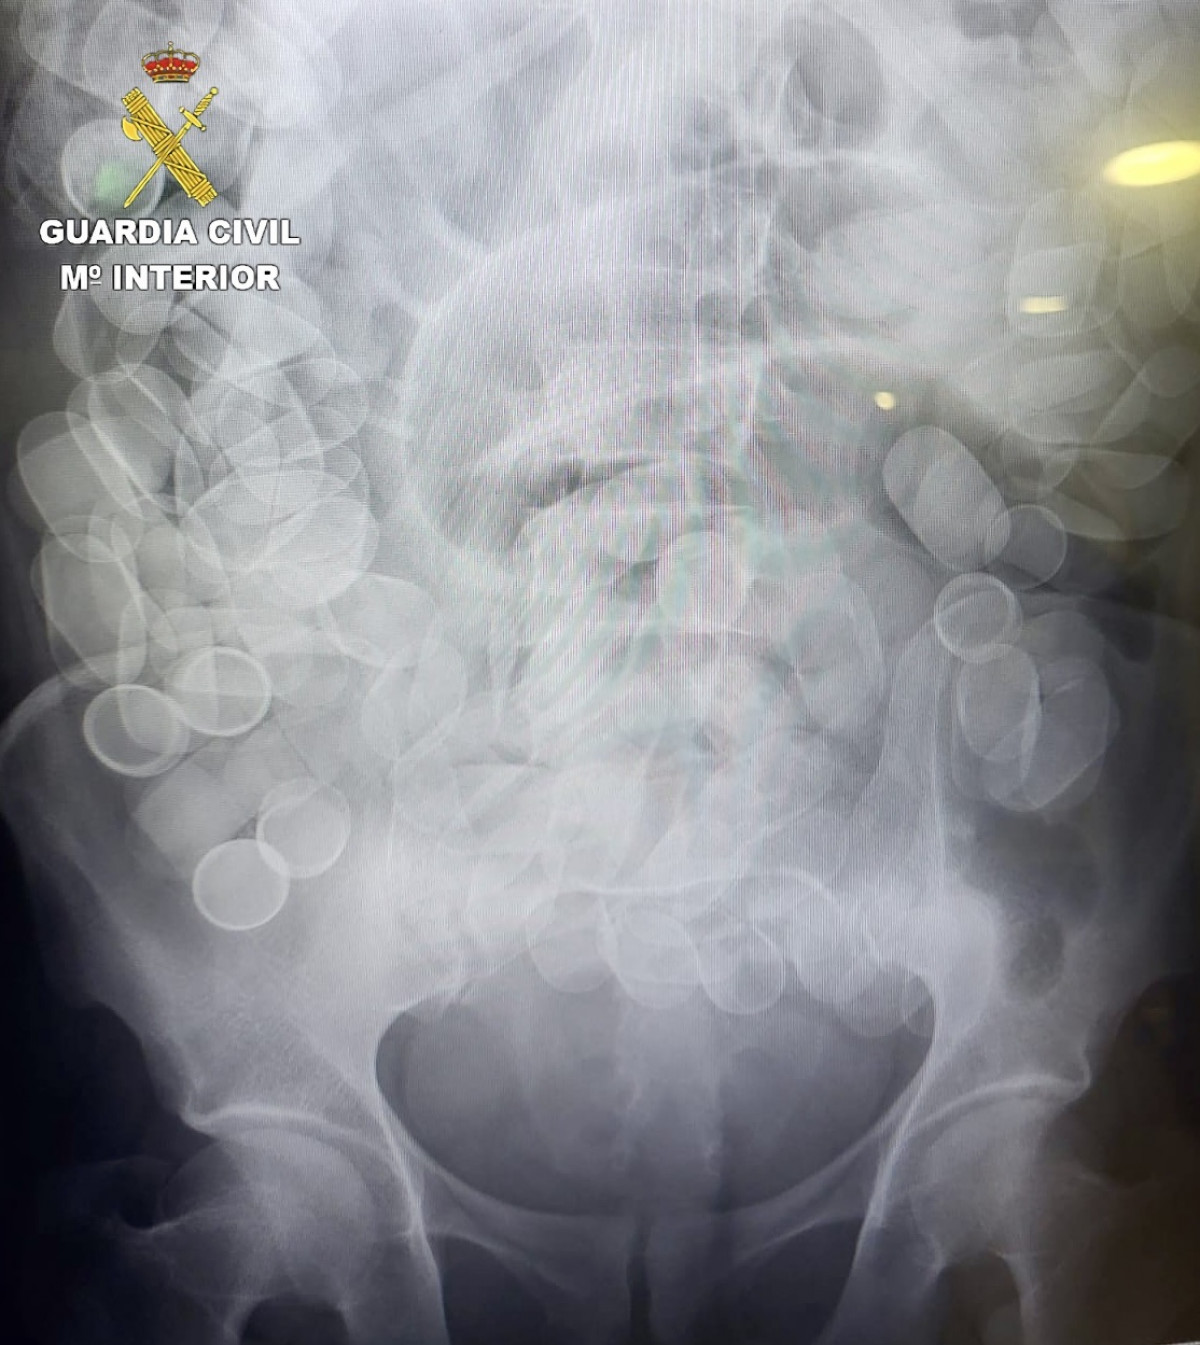

La prueba de rayos X practicada a un pasajero detenido en el Aeropuerto de El Prat de Barcelona que había ingerido 153 cilindros de cocaína - GUARDIA CIVIL

La Guardia Civil ha detenido en el Aeropuerto Josep Tarradellas-Barcelona El Prat a un pasajero que había ingerido 153 cilindros de cocaína con un peso total de un 1.480 gramos, según ha informado el instituto armado en un comunicado este miércoles.

Una vez detenido, los agentes comprobaron que su estado de salud no era bueno, por lo que fue trasladado rápidamente al Hospital de Bellvitge donde se confirmó la presencia de cuerpos extraños en su interior y tuvo que ser intervenido de urgencia porque algunos de los cilindros se habían roto.